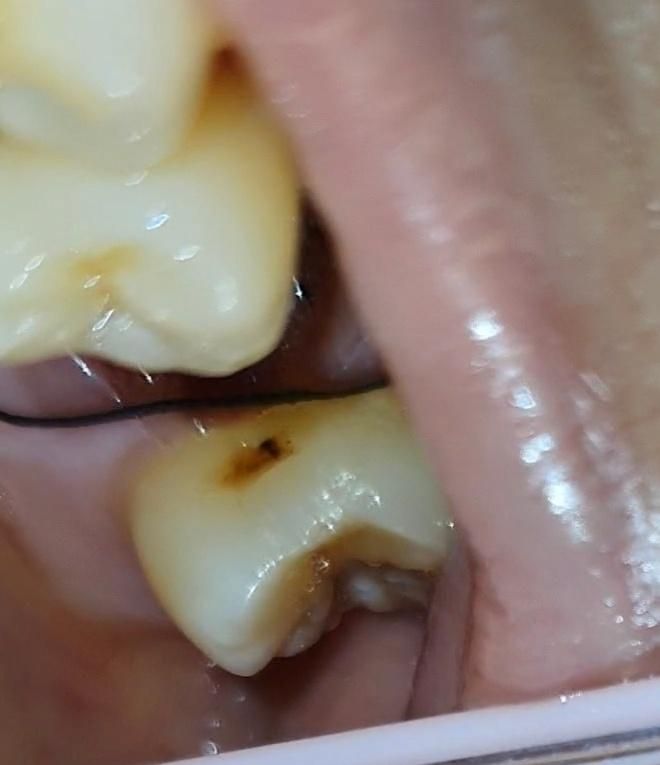

발치한 치아 앞뒤 치아 옆면 충치? 착색?

앞뒤로 치아 옆이 긁힘? 살짝 패여있는데

충치인지 착색인건지...

• 2번 째 사진

사진에 보이는건 치아 옆면에 충치가 잇는거 같습니다. 엑스레이 촬영후 치료를 하시는게 좋을것같습니다.

스케일링하면서 주위 착색 제거하고 착색제거후 남은 충치는 간단한 충치치료를 해주시면 좋을거 같습니다. 충치 치료 완료후 연마를 시행하게 되면 치면이 더 부드러워져서 음식물이 달라붙는 현상도 많이 감소할거같습니다. 근처 치과에서 상담후 치료 진행하시면 될거 같습니다.

사진으로만 봤을 경우에는 치아 표면에 작은 충치가 생긴것으로 보입니다. 이런 충치는 간단하게 치료를 할수도 있습니다.

둘 다 충치로 보여집니다. 보통 치아를 뽑고 나면 앞 뒤 치아에 발견하지 못한 충치가 많이 발견됩니다. 현재 상태에서는 특별히 접근이 어렵지 않으므로 간단히 레진 등으로 수복할 수 있는 정도이므로 임플란트나 다른 치료를 하기 전에 먼저 간단히 치료를 하는 것을 권해드립니다.

사진으로 봐서는 좀 애매하고 탐침 등의 기구로 긁어봤을때 긁히면 떼워주면 좋을 것 같습니다 깊은 충치는 아닌 것 같습니다